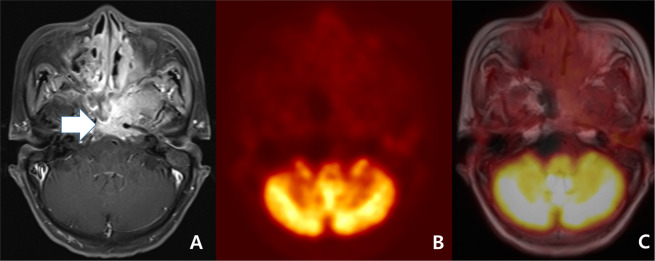

However, in spite of these advantages, we must be aware that PET/MRI also has various pitfalls. First, in even benign concordant cases, PET/MRI might have produced false negative results in cases such as small lesions (Fig. 1)10,20. Second, in even malignant concordant cases, PET/MRI might have produced false positive results in cases such as inflammatory lymph node or lymphoid hyperplasia that can be seen in a larger size on the MRI and as hypermetabolism on PET3,9,11,20. Third, in discordant cases, MRI has been known to show better diagnostic accuracy in necrotic tumor, perineural spread, and tumor with low metabolic activity such as low grade lymphoma (Fig. 3)4,10,14,26,33–35. In contrast, PET might have better advantage in small but FDG-avid tumor and work-up for metastasis of unknown origin (Fig. 2)9,11,36. In the discordant cases of our study, PET tended to be correct in nodal lesions but MRI tended to be correct in non-nodal lesions.

Figure 3.

Follow-up work-up of a 69-year-old woman with nasopharyngeal carcinoma treated by concurrent chemoradiation therapy. (A) A transverse fat-suppression contrast enhanced MRI revealed enhancing lesion at nasopharynx and mid skull base (arrow). The lesion decreased in size when compared to pre-treatment MRI (not displayed). However, a neuroradiologist scored the lesion as 5 (definitely malignant). (B) The PET reveals equivocally mild metabolism (maximal SUV: 2.9). Considering the interval significant decrease of the metabolism (maximal SUV on pre-treatment PET: 9.3 [not displayed]), a nuclear medicine specialist scored the lesion as 2 (probably benign). (C) A consensus score of PET/MRI for the lesion at nasopharynx and mid skull base was 4 (probably malignant) and biopsy specimen revealed a residual tumor.